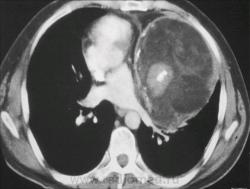

Иллюстрация 9.

Иллюстрация 10.

Иллюстрация 11.

31. - саркоидоз.

31 - саркоидоз...

31-саркоидоз/ЛГМ

31 - Саркоидоз.